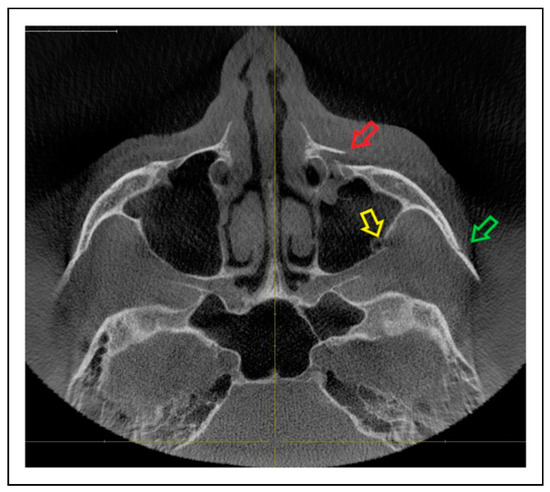

Patterns of ZMO Fractures Regarding the Anatomic Sutures of the Zygoma

- Unisutural fracture (isolated fracture of a single anatomic suture of the zygoma):

- Zygomaticomaxillary suture (ZM)

- Infraorbital rim (IOR)

- Zygomaticofrontal suture (ZF)

- Zygomaticosphenoidal suture (ZS)—the anterolateral orbital floor

- Zygomaticotemporal suture (ZT)

- Tetrasutural fracture with the following fracture line combinations:

- ZM suture + IOR + ZF suture + ZS suture

- ZM suture + IOR + ZS suture + ZT

- IOR + ZF suture + ZS suture + ZT

- Complete ZMO fracture involving all 5 anatomic sutures of the zygoma:

- ZM suture + IOR + ZF suture + ZS suture + ZT